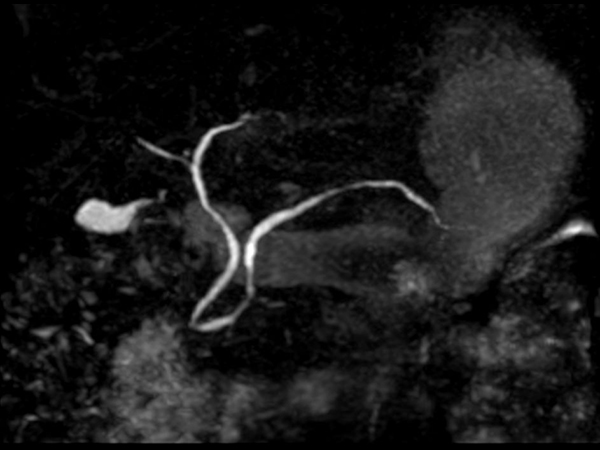

bTRANCE non-CE MRA (tumble)

-

bTRANCE non-CE MRA (spin)